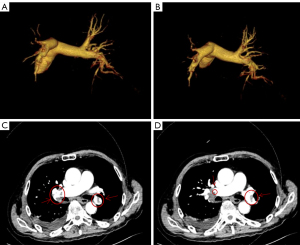

On Day 3, imaging confirmed pulmonary embolism via pulmonary vascular CTA, and ultrasound of both lower extremities revealed multiple arterial plaques and thrombosis in the intermuscular veins of the right lower leg (Figures 3,4). Anticoagulation therapy was intensified with nadroparin (4,100 IU Q12H). On Day 4, the patient developed respiratory failure [peripheral oxygen saturation (SpO2) <90%], his D-dimer levels exceeded 50,000 µg/L, and his platelet count dropped to 37×109/L, presenting a “thrombosis-bleeding” treatment dilemma. Thrombocytopenia was initially attributed to eosinophil-mediated consumptive coagulopathy, with serial platelet counts showing a decline from 64×109/L (admission) to 37×109/L (Day 4). Heparin-induced thrombocytopenia (HIT) was ruled out due to: (I) the onset of thrombocytopenia within 48 hours of nadroparin initiation, which was shorter than the typical 5–10-day latency period for HIT (19); and (II) a platelet count decline of <50% from the baseline, which was below the diagnostic threshold for HIT (20).